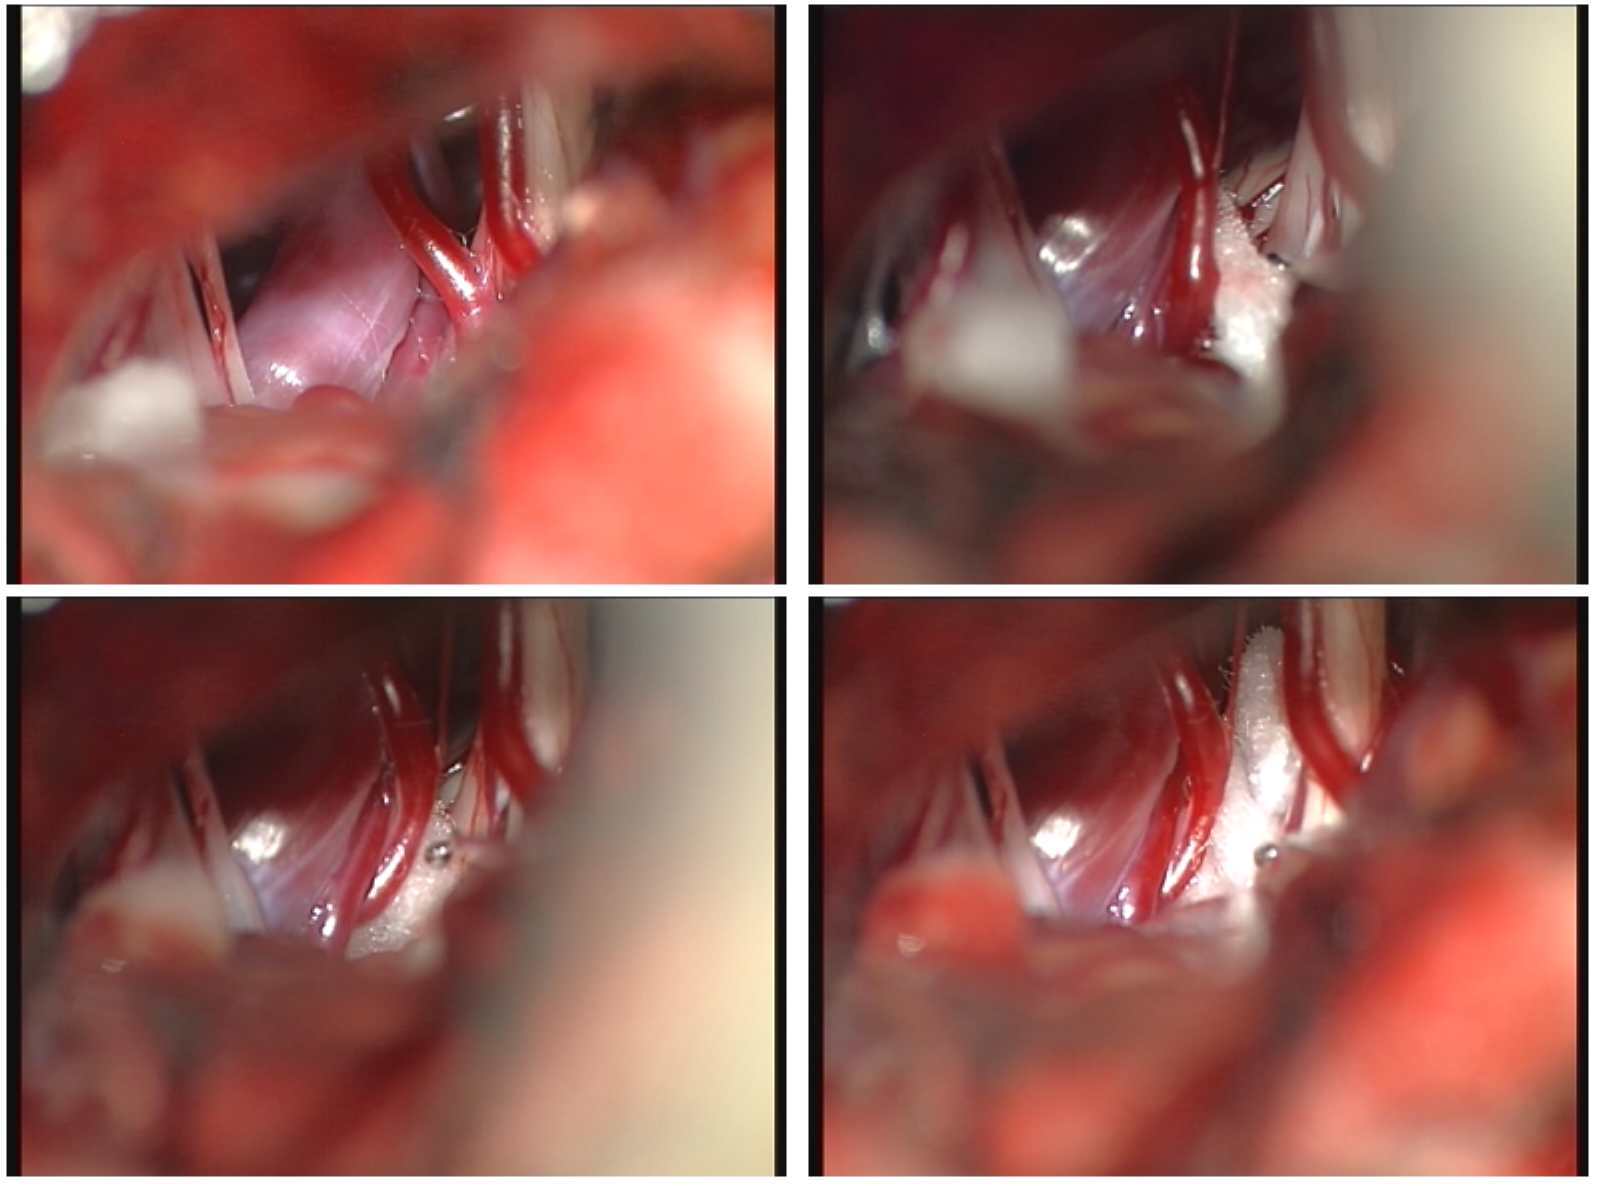

经颅后窝面神经微血管解压术因其疗效确切,不易复发,极少造成面部感觉障碍,并且随着手术显微镜的发展,其出现并发症的几率很低,而越来越为更多的患者所接受。该类手术的核心原理是:在手术显微镜下微创操作,分离压迫面神经根部的血管襻,然后插入特制的垫片将血管与神经隔离开来,彻底去除了血管对面神经的压迫,解除了患者的痛苦,是目前国际上公认的面肌痉挛疾病最有效方法。微血管减压术,其治疗面肌痉挛的总有效率为90%,且复发率低,为面肌痉挛患者带来了曙光。

术中过程